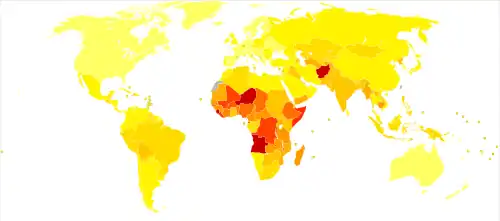

Epidemiology

Pneumonia is a common illness affecting approximately 450 million people a year and occurring in all parts of the world.[12] It is a major cause of death among all age groups resulting in 4 million deaths (7% of the world's total death) yearly.[12][13] Rates are greatest in children less than five, and adults older than 75 years.[12] It occurs about five times more frequently in the developing world than in the developed world.[12] Viral pneumonia accounts for about 200 million cases.[12] In the United States, as of 2009, pneumonia is the 8th leading cause of death.[24]

Children

In 2008, pneumonia occurred in approximately 156 million children (151 million in the developing world and 5 million in the developed world).[12] In 2010, it resulted in 1.3 million deaths, or 18% of all deaths in those under five years, of which 95% occurred in the developing world.[12][23][147] Countries with the greatest burden of disease include India (43 million), China (21 million) and Pakistan (10 million).[148] It is the leading cause of death among children in low income countries.[12][13] Many of these deaths occur in the newborn period. The World Health Organization estimates that one in three newborn infant deaths is due to pneumonia.[149] Approximately half of these deaths can be prevented, as they are caused by the bacteria for which an effective vaccine is available.[150] The IDSA has recommended that children and infants with symptoms of CAP should be hospitalized so they have access to pediatric nursing care.[151] In 2011, pneumonia was the most common reason for admission to the hospital after an emergency department visit in the U.S. for infants and children.[152]